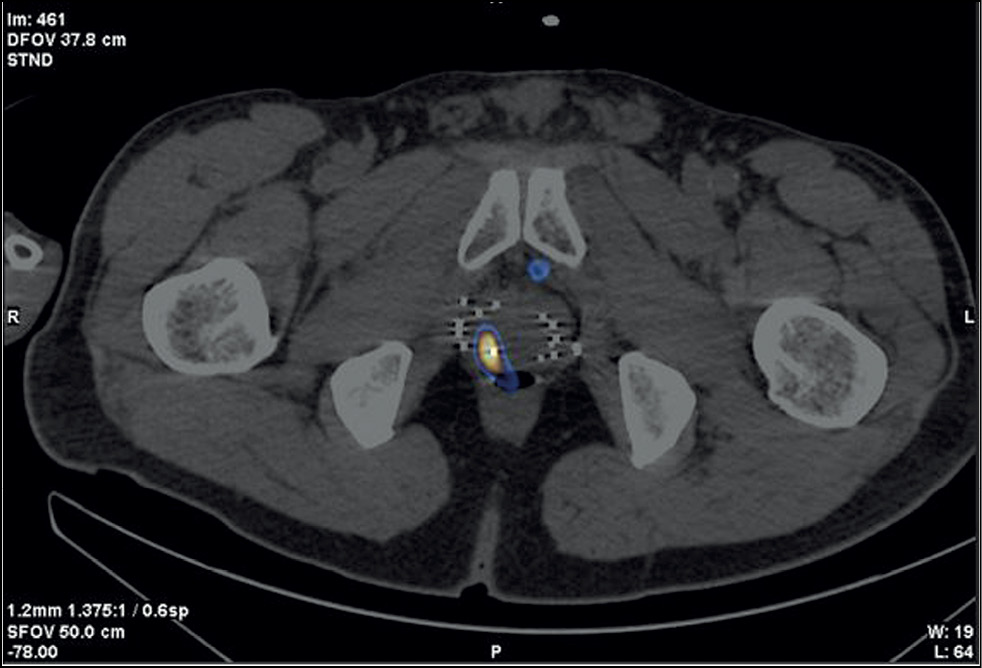

Case report 5

Patient G., 70 years old, was admitted with prostate cancer (diagnosed in 2005), T2a, adenocarcinoma, Gleason 6 (3 + 3). CT-guided brachytherapy was successfully performed in 2005. The PSA level has increased (1.94–2.31 ng/mL) since 2017. Because of this growth, ultrasound, TRUS, CT, and contrast-enhanced MRI were performed; no data for a local recurrence or another cause of PSA growth were obtained. When the PSA level reached 2.63 ng/mL, SPECT/CT with 99mTc-HYNI-PSMA was performed (Figure 6). Results showed a 15-mm3 site of RP accumulation, and a targeted biopsy of a recurrent prostate carcinoma lesion was performed based on its SPECT/CT location. Adenocarcinoma was confirmed histologically, Gleason 6 (3 + 3). On March 10, 2020, a brachytherapy with reimplantation of 125I microsources was performed. The follow-up examination (December 2022) showed a PSA level of 0.21 ng/mL.

Fig. 6. Patient G., 70 years old, SPECT/CT with 99mTc-HYNIC-PSMA: Site of radiopharmaceutical accumulation in the posterolateral part of the peripheral zone of the middle part of the right prostate lobe. Multiple rods in the prostate gland were implanted during previous brachytherapy.

In this case, SPECT/CT with 99mTc-HYNIC-PSMA enabled prostate carcinoma–targeted biopsy and precision brachytherapy.